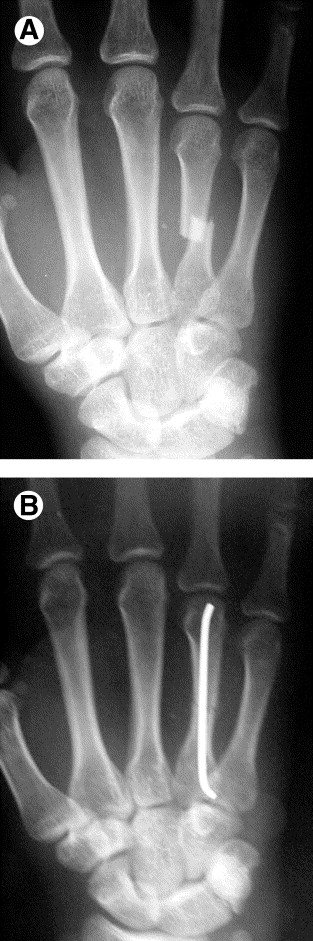

Upload Date: March 31, 2019 Full Size Image Dimensions: 313 × 941 Image Parent Post: Κατάγματα άνω άκρου

8b.Διαδερμική οστεοσύνθεση κατάγματος μετακαρπίου